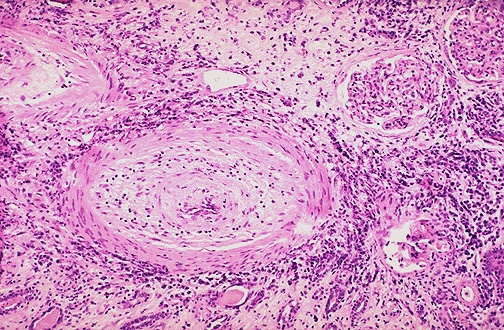

| At high magnification, the renal arteries with chronic vascular rejection are markedly thickened and fibrotic. There is interstitial fibrosis and chronic inflammation. Such chronic rejection usually occurs slowly over several months to years following transplantation. This form of rejection, unlike acute cellular rejection, is difficult to treat. |